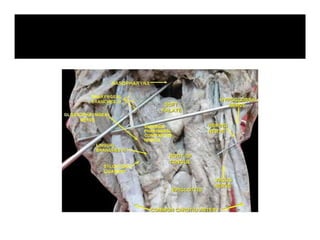

The nerve enters

the pharynx in the

2nd gap

(between

superior & middle

constrictor muscle)

then it passes

deep to hyoglossus

muscle & divides

into its branches.